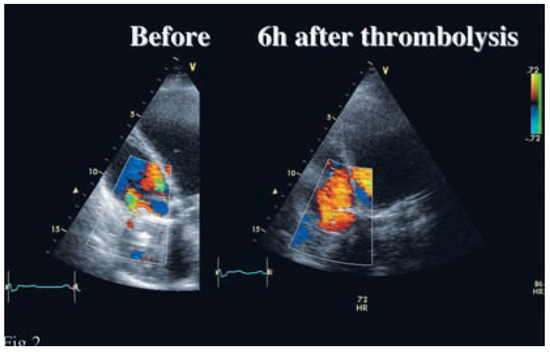

Coronary CT angiography (CTA) is emerging as a highly effective alternative imaging technique for the assessment of coronary artery disease (CAD). The rapid evolution of multidetector CT scanners has lead to major improvement in temporal resolution o...